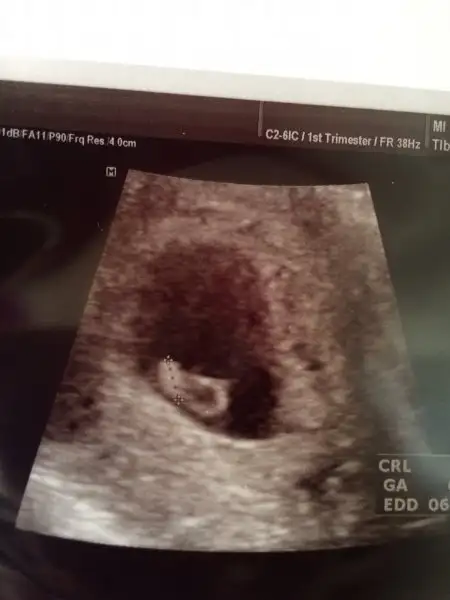

Havalianne__ canim zahmet olmazsa benim kesemi de yorumlar misin? 6+1 karindan

Foto eklemeyi unutmusumm ya@SLVESTER 6+4 gunluguz